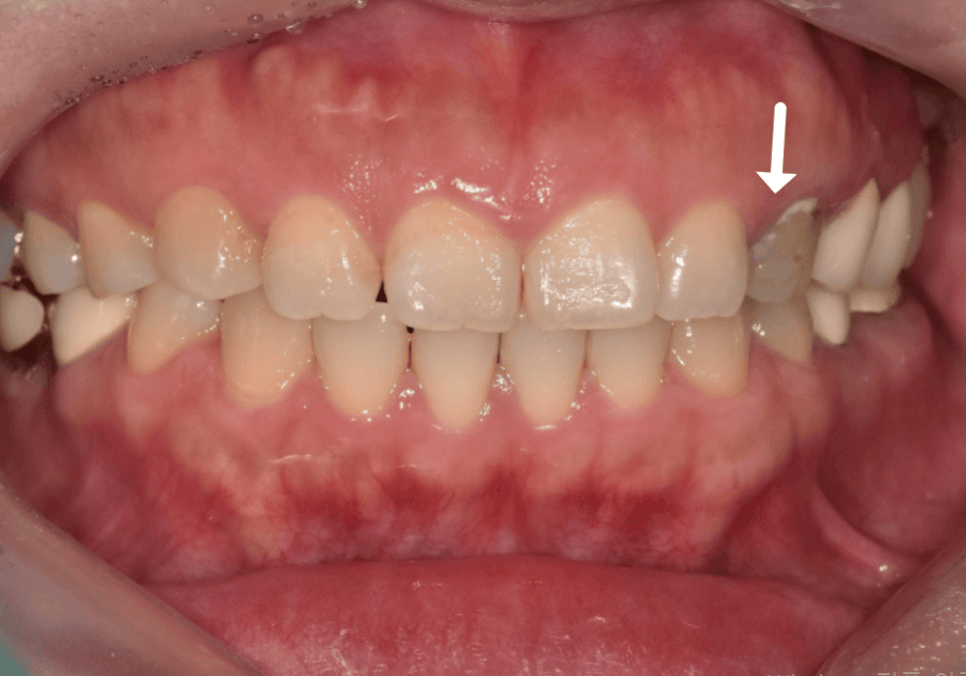

실제 최근 저희 치과를 찾으신

환자분의 사례를 말씀드릴게요.

이 환자분은 오래전 왼쪽 송곳니(#23)

신경치료를 받은 뒤 레진으로 때워서

쓰고 계셨다고 해요.

시간이 지날수록

송곳니 색이 유독 어둡고

검게 변하는 것 같아 때워둔 레진에

문제가 생긴 줄 알고 내원하셨는데요.

검사 결과, 레진이 원인이 아닌

앞서 말씀드린 것처럼 신경 치료 후

내부 조직이 산화되어 내부적으로 검게 변해

비춰 보이는 것이었어요.

뿐만 아니라, 레진과 치아 사이의 미세한 틈으로

2차 충치까지 진행되고 있었기에,

더는 미루지 않고 크라운 치료를

진행하기로 했습니다.

옆 치아들과 비교했을 때,

확실히 어둡고 탁한 색조가

치아 깊숙한 곳까지 배어 있는 모습인데요,

이처럼 내부 변색이 심할 때는